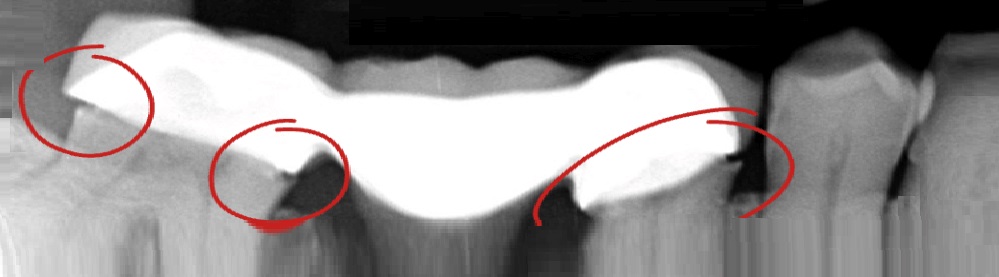

Dental Bridge at Archer Dental